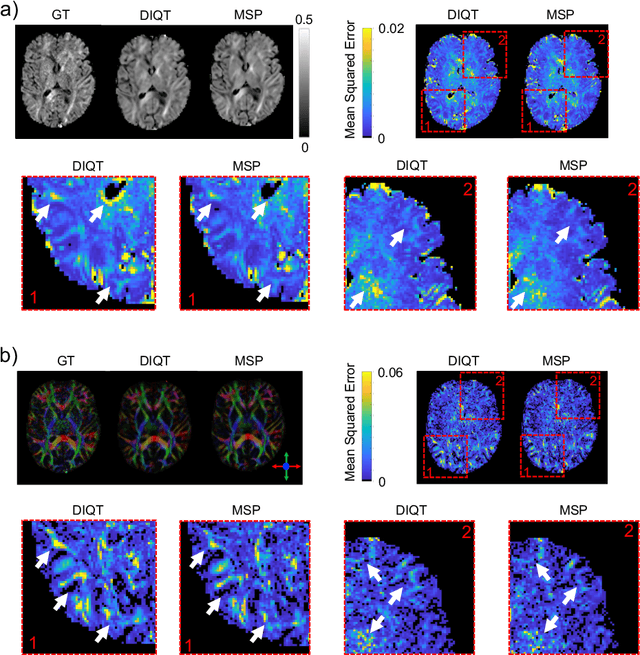

Abstract:In this paper, we introduce multi-task learning (MTL) to data harmonization (DH); where we aim to harmonize images across different acquisition platforms and sites. This allows us to integrate information from multiple acquisitions and improve the predictive performance and learning efficiency of the harmonization model. Specifically, we introduce the Multi Stage Prediction (MSP) Network, a MTL framework that incorporates neural networks of potentially disparate architectures, trained for different individual acquisition platforms, into a larger architecture that is refined in unison. The MSP utilizes high-level features of single networks for individual tasks, as inputs of additional neural networks to inform the final prediction, therefore exploiting redundancy across tasks to make the most of limited training data. We validate our methods on a dMRI harmonization challenge dataset, where we predict three modern platform types, from one obtained from an old scanner. We show how MTL architectures, such as the MSP, produce around 20\% improvement of patch-based mean-squared error over current state-of-the-art methods and that our MSP outperforms off-the-shelf MTL networks. Our code is available https://github.com/sbb-gh/ .